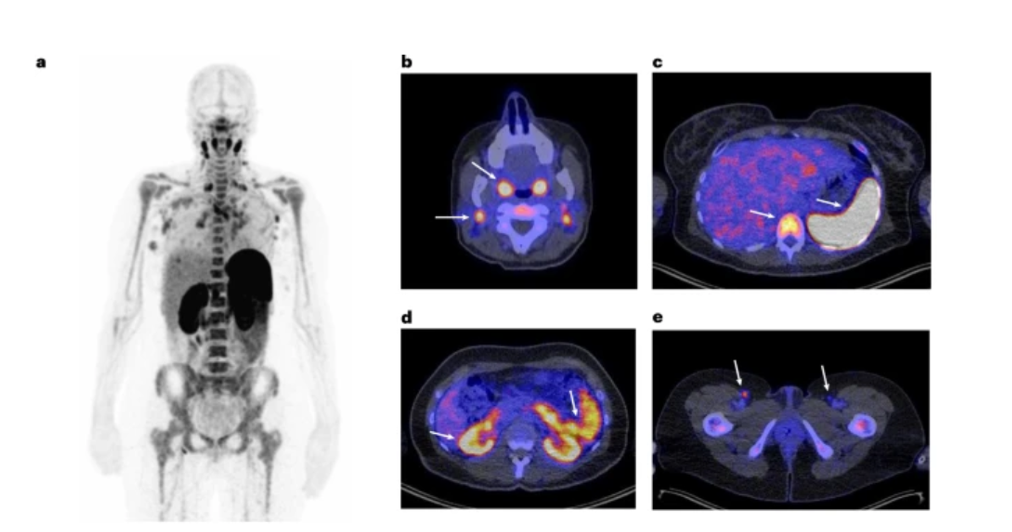

مهارکننده های نقاط بازرسی ایمنی با ایمنی به واسطه ی سلول های تقویت کننده CD8+ Tمسیر درمان سرطان را با تغییرات اساسی مواجه کرده است. تاکنون توزیع سراسری سلول هایCD8+ T(بیومارکری در پاسخ به مهارکننده های نقاط بازرسی ایمنی) به میزان کمی شناخته شده است. در یک تحقیق مسائل ایمنی، دوز تصویربرداری، زمان بندی، فارماکوکینتیک و ایمنی زایی آنتی بادی اختصاصی CD8لیبل شده با زیرکونیوم-89 و ردیاب در تصیویربرداری PET scanبه نام 89ZED88082Aدر بیمارانی با تومورهای جامد قبل و حدود 30 روز بعد از درمان با مهارکننده های نقاط بازرسی ایمنی بررسی شدند. در این تحقیق هیچ عارضه جانبی مبتنی بر ردیاب مشاهده نشد. تصویر برداری PET scanبا mg10 آنتی بادی نشاندار 89ZED88082Aدر بافت های لنفوئیدی نرمال و بافت های توموری در سرتاسر بدن بین بیماران دو روز قبل از تزریق متفاوت بوده است. ورود به سلول دارو در تومورهای التهابی بیشتر از ایمونوفنوتایپ است. اثر رادیواکتیویته بافت در نواحی که بیان CD8توسط ایمونوهیستوشیمی تأیید شده است، متمرکز می شود. بیمارانی که مجدد تصویر برداری کردند به طور میانگین تفاوتی از نظر ورود عامل های نشاندار شده در مقایسه با کنترل از خود نشان ندادند؛ درحالیکه تومورهای تک تغییرات متفاوتی را مستقل از پاسخ تومور از خود نشان دادند. این داده های تصویری هتروژنیسیتی فراوانی را در توزیع و دینامیک دارویی سلول های CD8+Tدر بیماران را از خود نشان دادند. در نتیجه 89ZED88082Aمی تواند دینامیک پیچیده سلول های CD8+Tرا در ارتباط با مهارکننده های نقاط بازرسی ایمنی مشخصه یابی کند و درمان های ایمنوتراپی را بهبود بخشد. منبع: https://www.nature.com/articles/s41591-022-02084-8